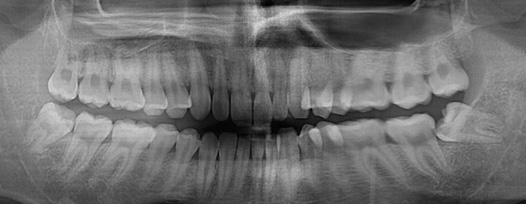

치주치료

청담네오플란트는 치주치료를 통하여 치아를 살릴 수 있는 기회를 놓치지 않습니다.

치주염(잇몸병)은 치아에 붙어있는 치석 및 세균 등에 의한 염증반응으로 잇몸뼈가 상실되는 질환을 말합니다.

초기에는 잇몸이 붓거나 잇몸에서 피가 나는 증상이 나타나며 계속 방치하면 치아를 발치해야 할 수도 있습니다.

치주치료는 이러한 치석 및 세균 등을 제거하여 잇몸뼈를 안정된 상태로 유지하는 시술을 말하며, 청담네오플란트에서는 치의학박사 / 전문의가 직접 시술하고 있습니다.